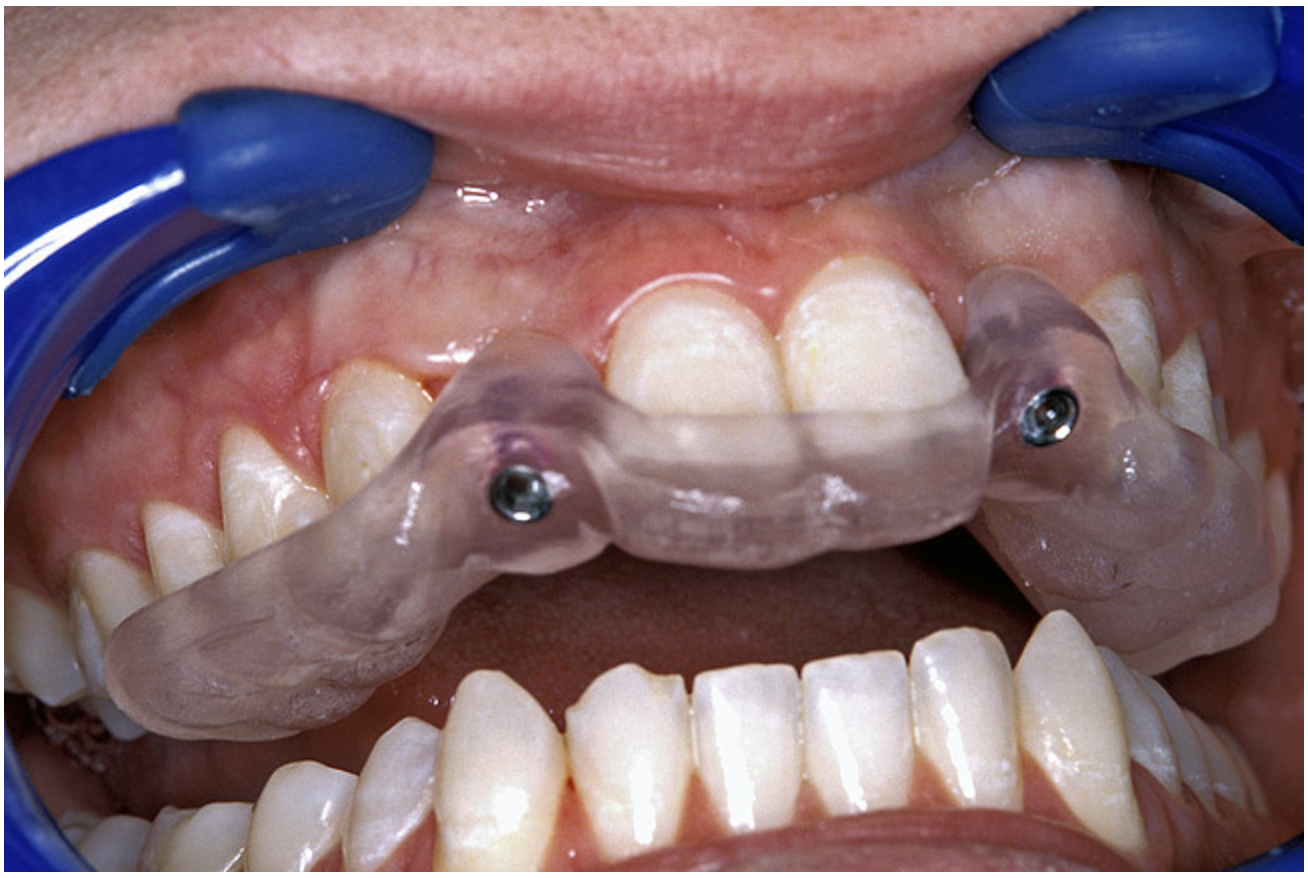

The 3.7-mm diameter Tapered Screw-Vent implant drilling sequence required three drills: pilot, intermediate, and final sizing. Thus, three separate templates were fabricated to accommodate these sizes. The templates were removed easily and replaced with the next sequential size in less time than it takes to change the drill on the surgical handpiece. After the osteotomies had been completed, the implants were delivered to the site (Figure 16A and Figure 16B). For this internal hex connection implant, the author r.commends that the flat of the antirotational hex be positioned to the facial for proper orientation of the restorative components (Figure 17A). Preprepared margins were created from a milled titanium fixture mount transfer post, which was delivered to the implant as support for an immediate transitional restoration. The facial “dot” helped confirm the orientation of the abutment to the facially positioned flat side of the internal hex connection (Figure 17B). Before cementation of the transitional acrylic restorations, a closed-tray, fixture-level impression was made, and a soft-tissue model fabricated.

Figure 16a  After (A) the osteotomies were completed, (B) the implants were placed.

Figure 16a

Figure 16b  After (A) the osteotomies were completed, (B) the implants were placed.

Figure 16b

Figure 17a  By predetermining the necessary orientation of the restorative components, the implant’s antirotational hex was positioned correctly.

Figure 17a

Figure 17b  By predetermining the necessary orientation of the restorative components, the implant’s antirotational hex was positioned correctly.

Figure 17b